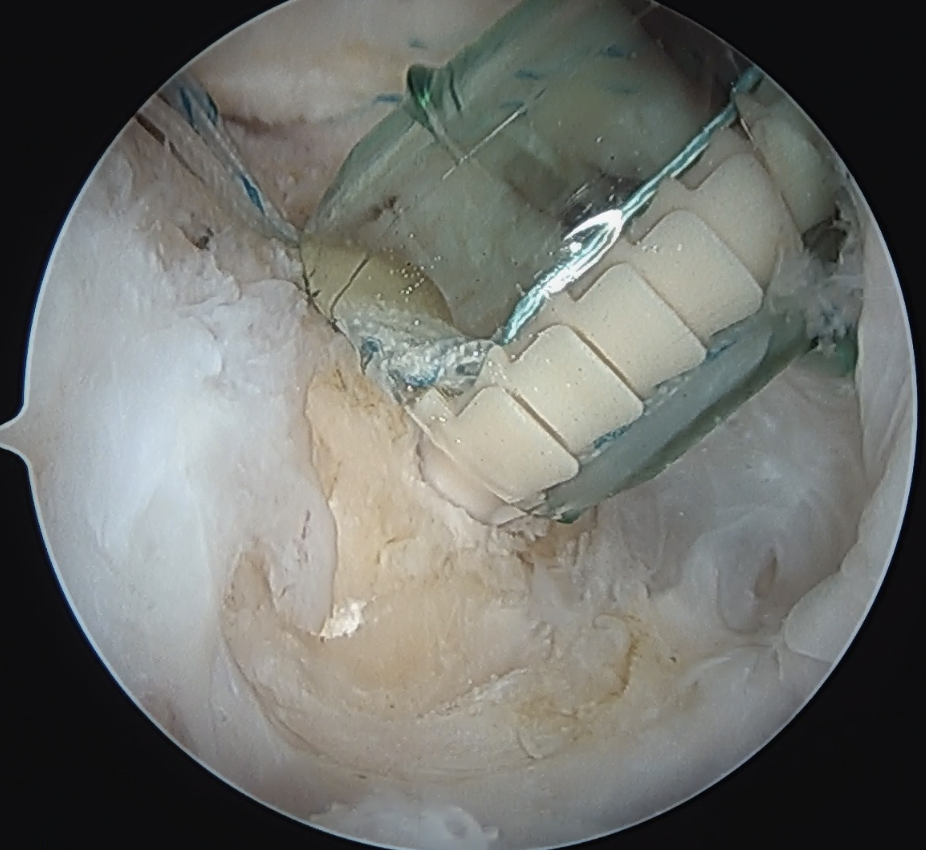

Arthroscopic Suture Bridge Cuff Repair

Double row / suture bridge

- use medial row sutures

- secure in knotless lateral row anchors

repairrepairrepair

Arthroscopic Cuff Suture Bridge RepairArthrscopic Cuff Repair